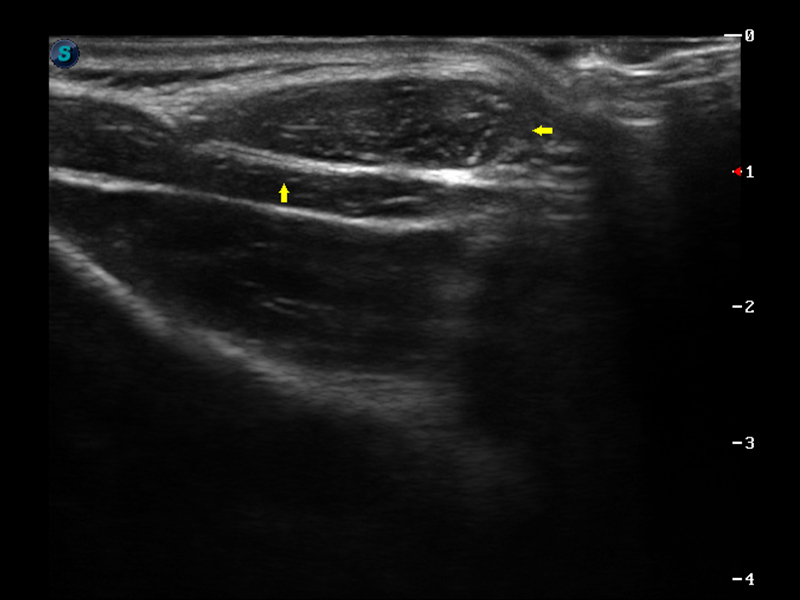

脉冲反相谐波成像